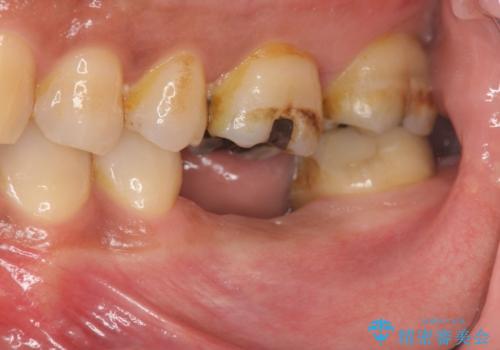

失った奥歯をインプラントで機能回復

- 失った歯の機能回復を希望され来院されました。

取り外しの必要な入れ歯、隣の歯を削る必要のあるブリッジに心理的抵抗があり、インプラントを用いて咬合機能を回復していくこととなりました。

元あった歯のようにしっかりと咬合機能が回復することができました。